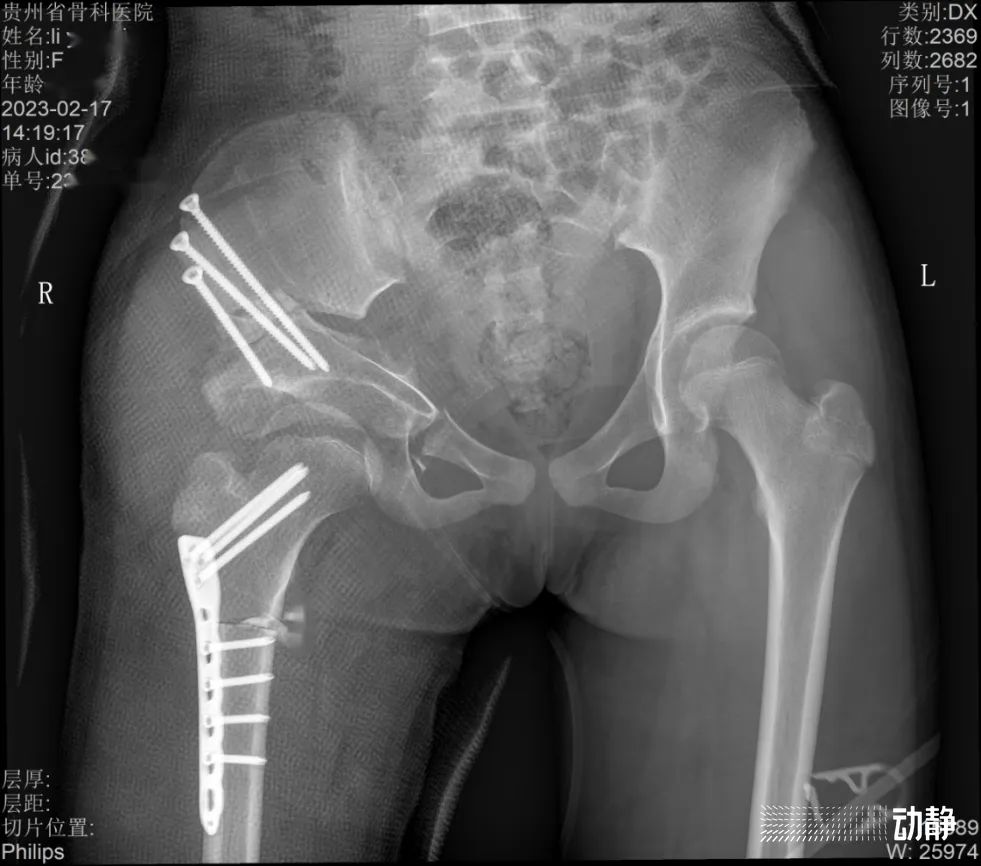

而第二例则是贵州首个采用了“积水潭入路微创三联”技术的髋关节发育不良孩子。据介绍,由于这个孩子病情发现比较晚,需要做三联截骨,把骨盆的三处都打断,是一个非常大的手术。

据了解,积水潭入路微创三联技术能够把手术的出血量降到原来的一半以下,从而实现病人恢复快的效果,同时也降低了对麻醉科、术后护理的要求。